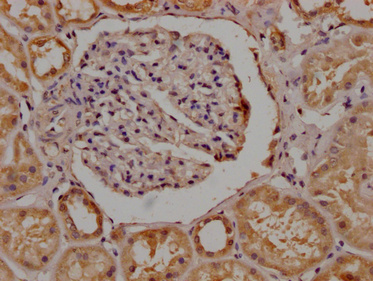

IHC image of CSB-PA836757OA01HU diluted at 1:200 and staining in paraffin-embedded human kidney tissue performed on a Leica BondTM system. After dewaxing and hydration, antigen retrieval was mediated by high pressure in a citrate buffer (pH 6.0). Section was blocked with 10% normal goat serum 30min at RT. Then primary antibody (1% BSA) was incubated at 4°C overnight. The primary is detected by a Goat anti-rabbit polymer IgG labeled by HRP and visualized using 0.05% DAB.